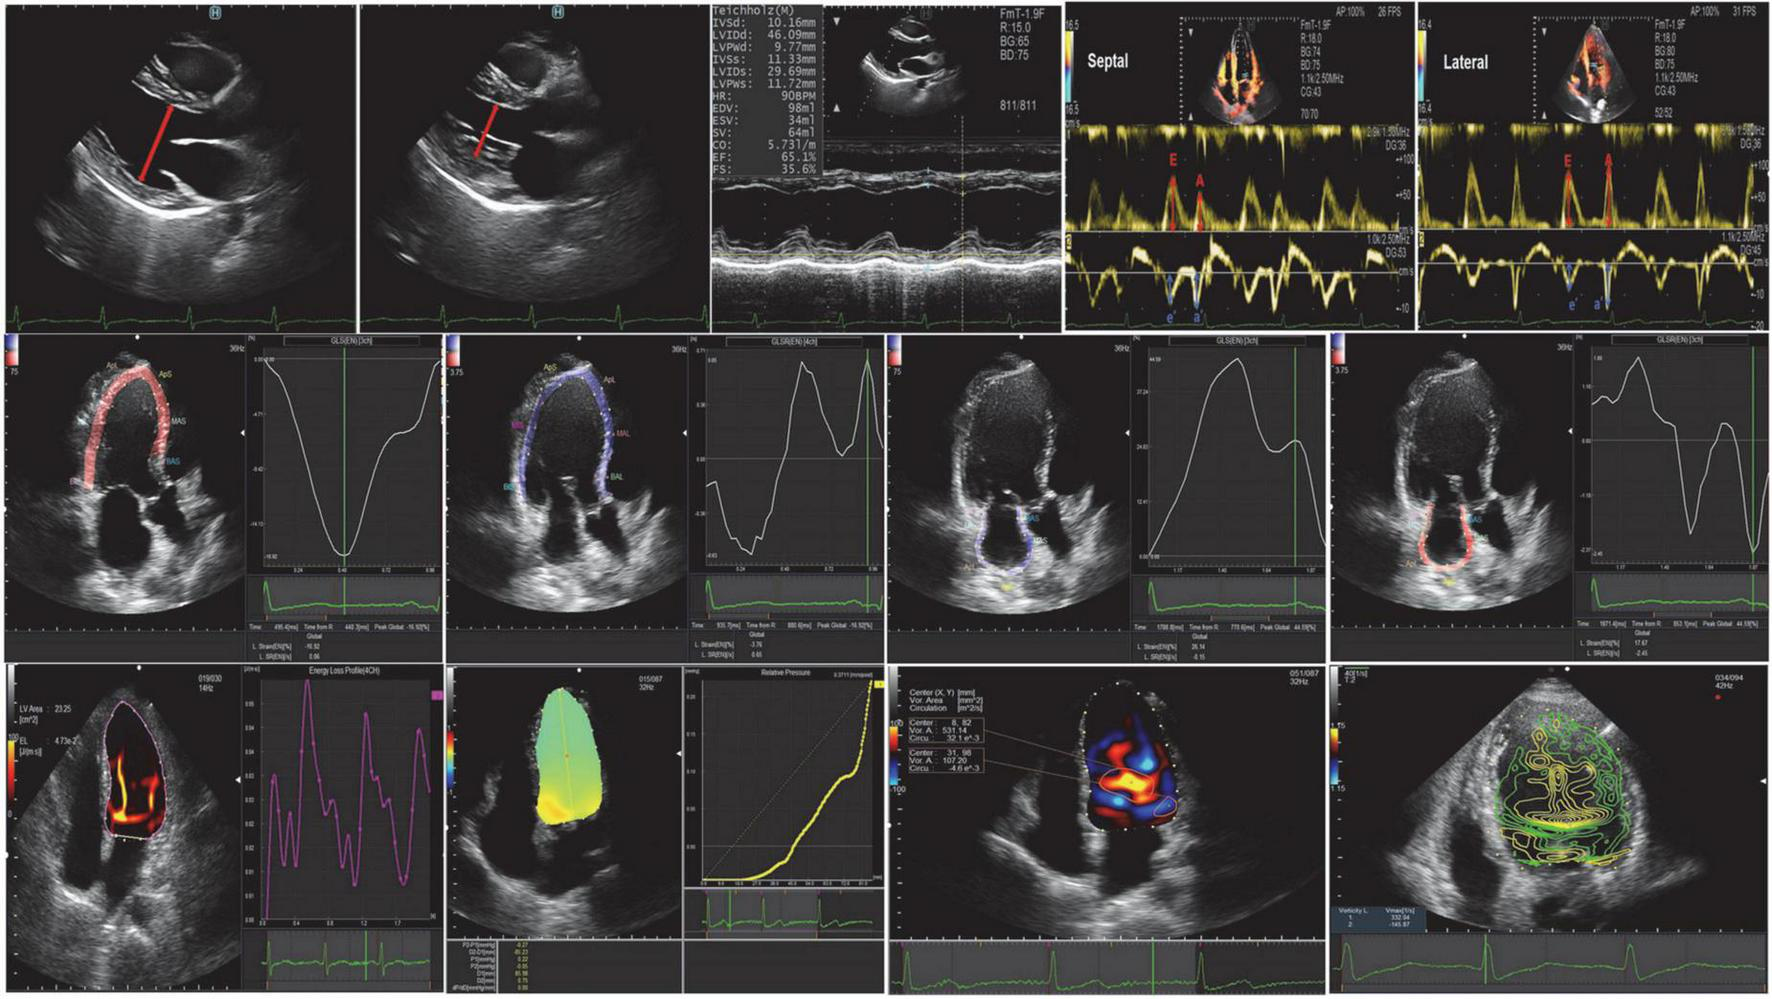

FIGURE 2

Conventional echocardiography, speckle-tracking echocardiography, and vortex flow mapping echocardiography.

Vector flow mapping

Images were analyzed using commercially available off-line software (DASRS1, Hitachi Aloka Medical Ltd., Tokyo, Japan). Using the initial point of the QRS complex as a reference point for image analysis, the LV endocardial border was tracked manually in end-diastolic frames and automatically by the software. Previous studies have limited validation studies (22–26), but the published data may contain useful clinical features. They included: (1) indexes of vortex from the flow-velocity curve, such as vortex area, circulation, maximum vorticity, and the vortex was automatically tracked and analyzed throughout the cardiac cycle (27, 28); (2) energy loss (EL) and mean energy loss (MEL), which were calculated as peak values (23, 24); (3) the intraventricular pressure difference (IVPD) and the intraventricular pressure gradient (IVPG), which were measured on a line that went through the center of the LV from the base to the apex (28, 29). The STE and VFM analysis were post-processed and analyzed by two professional VFM researchers (QL. SUN, Y. LI) (Figure 2).